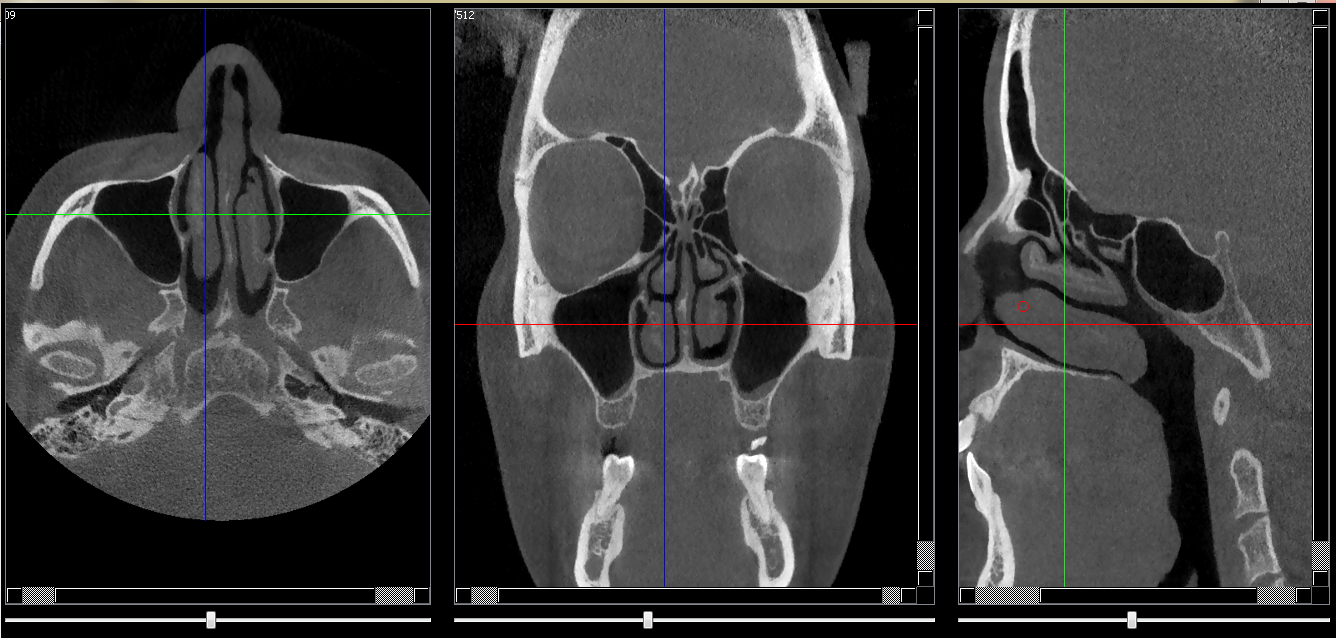

Cornet nasal inf

Repères anatomiques

- Coupe transversale

- Début : Palais dur

- Fin : Milieu du sinus

- Coupe frontale

- Début : Rhinopharynx

- Fin : Os nasale

- Coupe saggitale

- Début : Sinus maxillaire

- Fin : Septum nasal